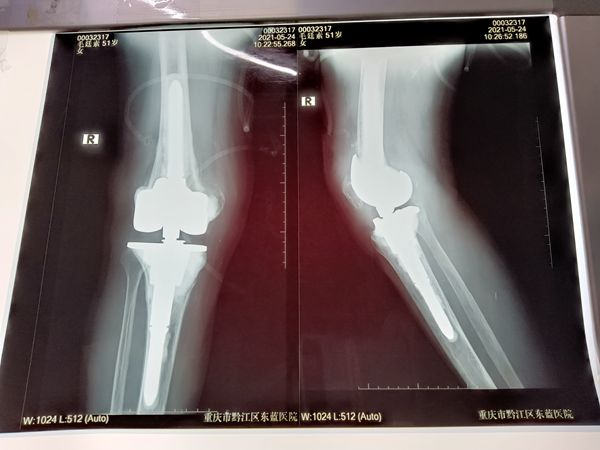

術后

好在冉祥從事骨科工作20余年,有著豐富的手術經驗。在經過充分術前計劃,定制關節假體,該院骨科團隊在冉祥的帶領下為其實施了翻修術。

由于膝蓋長期受損,內部組織結構已經面目全非,冉祥根據患者的骨骼完整程度,對股骨和脛骨進行了數次的精確截骨,并利用大量的金屬墊片進行骨的重建,同時重新為其安裝新的髖關節,其手術一氣呵成,不到兩個小時,患者順利完成了手術并被送回病房,目前已經下地行走,對其手術效果很是滿意。